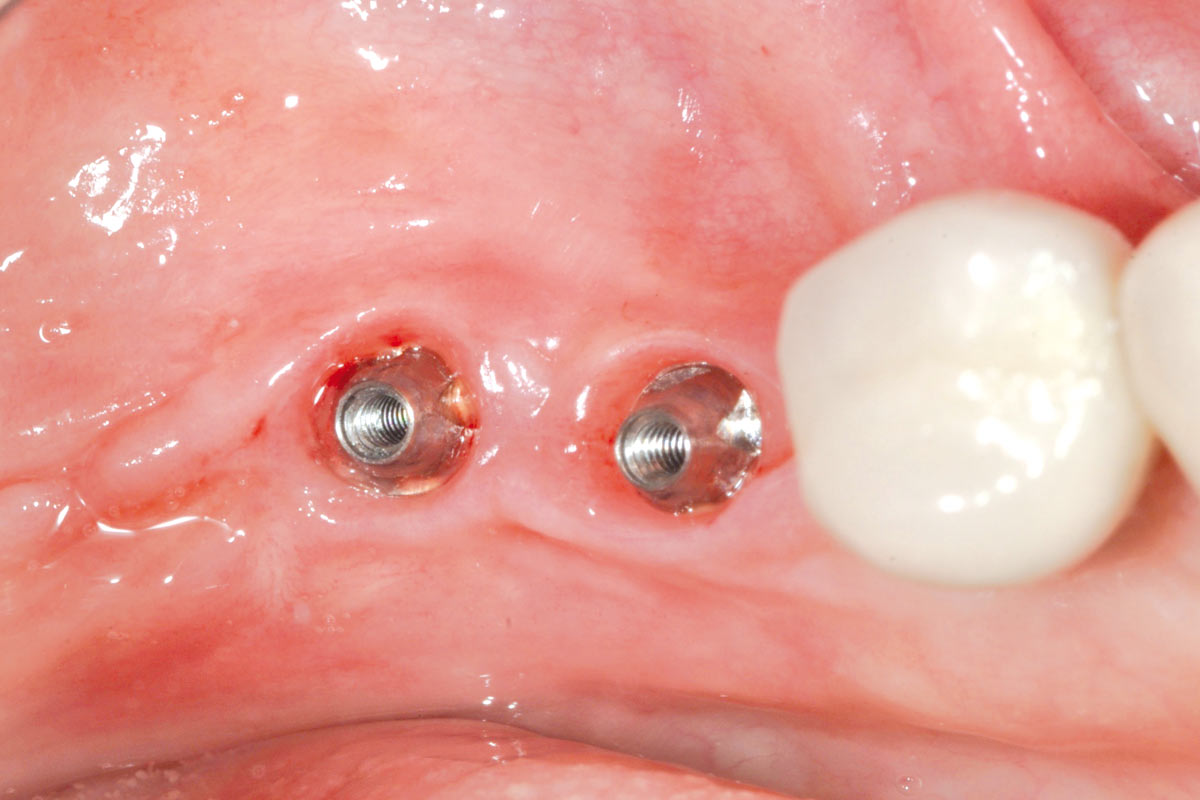

13/16 - Soft tissue profile at 7 weeksPeri-implant soft tissue thickening with mucoderm® - Dr. F. Rojas-Vizcaya